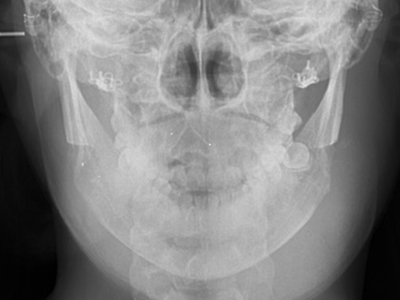

• 03

無需固定

X光拍攝下也乾淨利落

無需固定X光拍攝下也乾淨利落

WIAD方下巴縮小術案例

案例 01

WIAD的長曲線方下巴縮小術 + 皮質切除術可以明顯改善面部線條。

WIAD的長曲線方下巴縮小術

+ 皮質切除術可以明顯改善面部線條。

案例 02